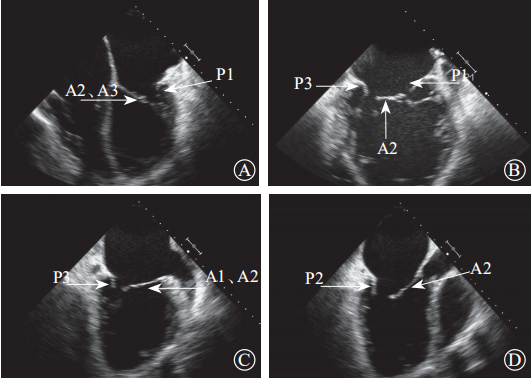

通过采集4个食管中段切面完整显示二尖瓣(图8)。(1)食管中段的四腔心切面,显示A2、A3和P1;(2)食管中段的二尖瓣交界处切面,显示A2、P1和P3;(3)食管中段的二腔心切面,显示A1、A2和P3;(4)食管中段的长轴三腔心切面,显示A2和P2。

MR介入治疗术前和术中,经常使用经食管三维超声心动图采集的X-plane双切面(包括二尖瓣交界处二腔心切面及三腔心切面)来评估二尖瓣解剖:二尖瓣交界处二腔心切面能清晰显示二尖瓣后叶P1及P3、前叶A2,而三腔心切面能清晰显示二尖瓣前叶A2、后叶P2。也可通过二尖瓣的“三维外科视野”立体显示二尖瓣前后叶(图9)。经食管二维、三维超声心动图通过上述切面评价MR的机制、程度以及部位,并确定瓣膜运动异常的扇叶。

图 8 经食管二维超声心动图显示二尖瓣瓣叶各扇叶 A. 食管中段的四腔心切面,显示 A2、A3 和 P1;B. 食管中段的二尖瓣交界处切面,显示 A2、P1和P3;C. 食管中段的二腔心切面,显示 A1、A2 和P3;D. 食管中段的长轴切面,显示 A2 和 P2